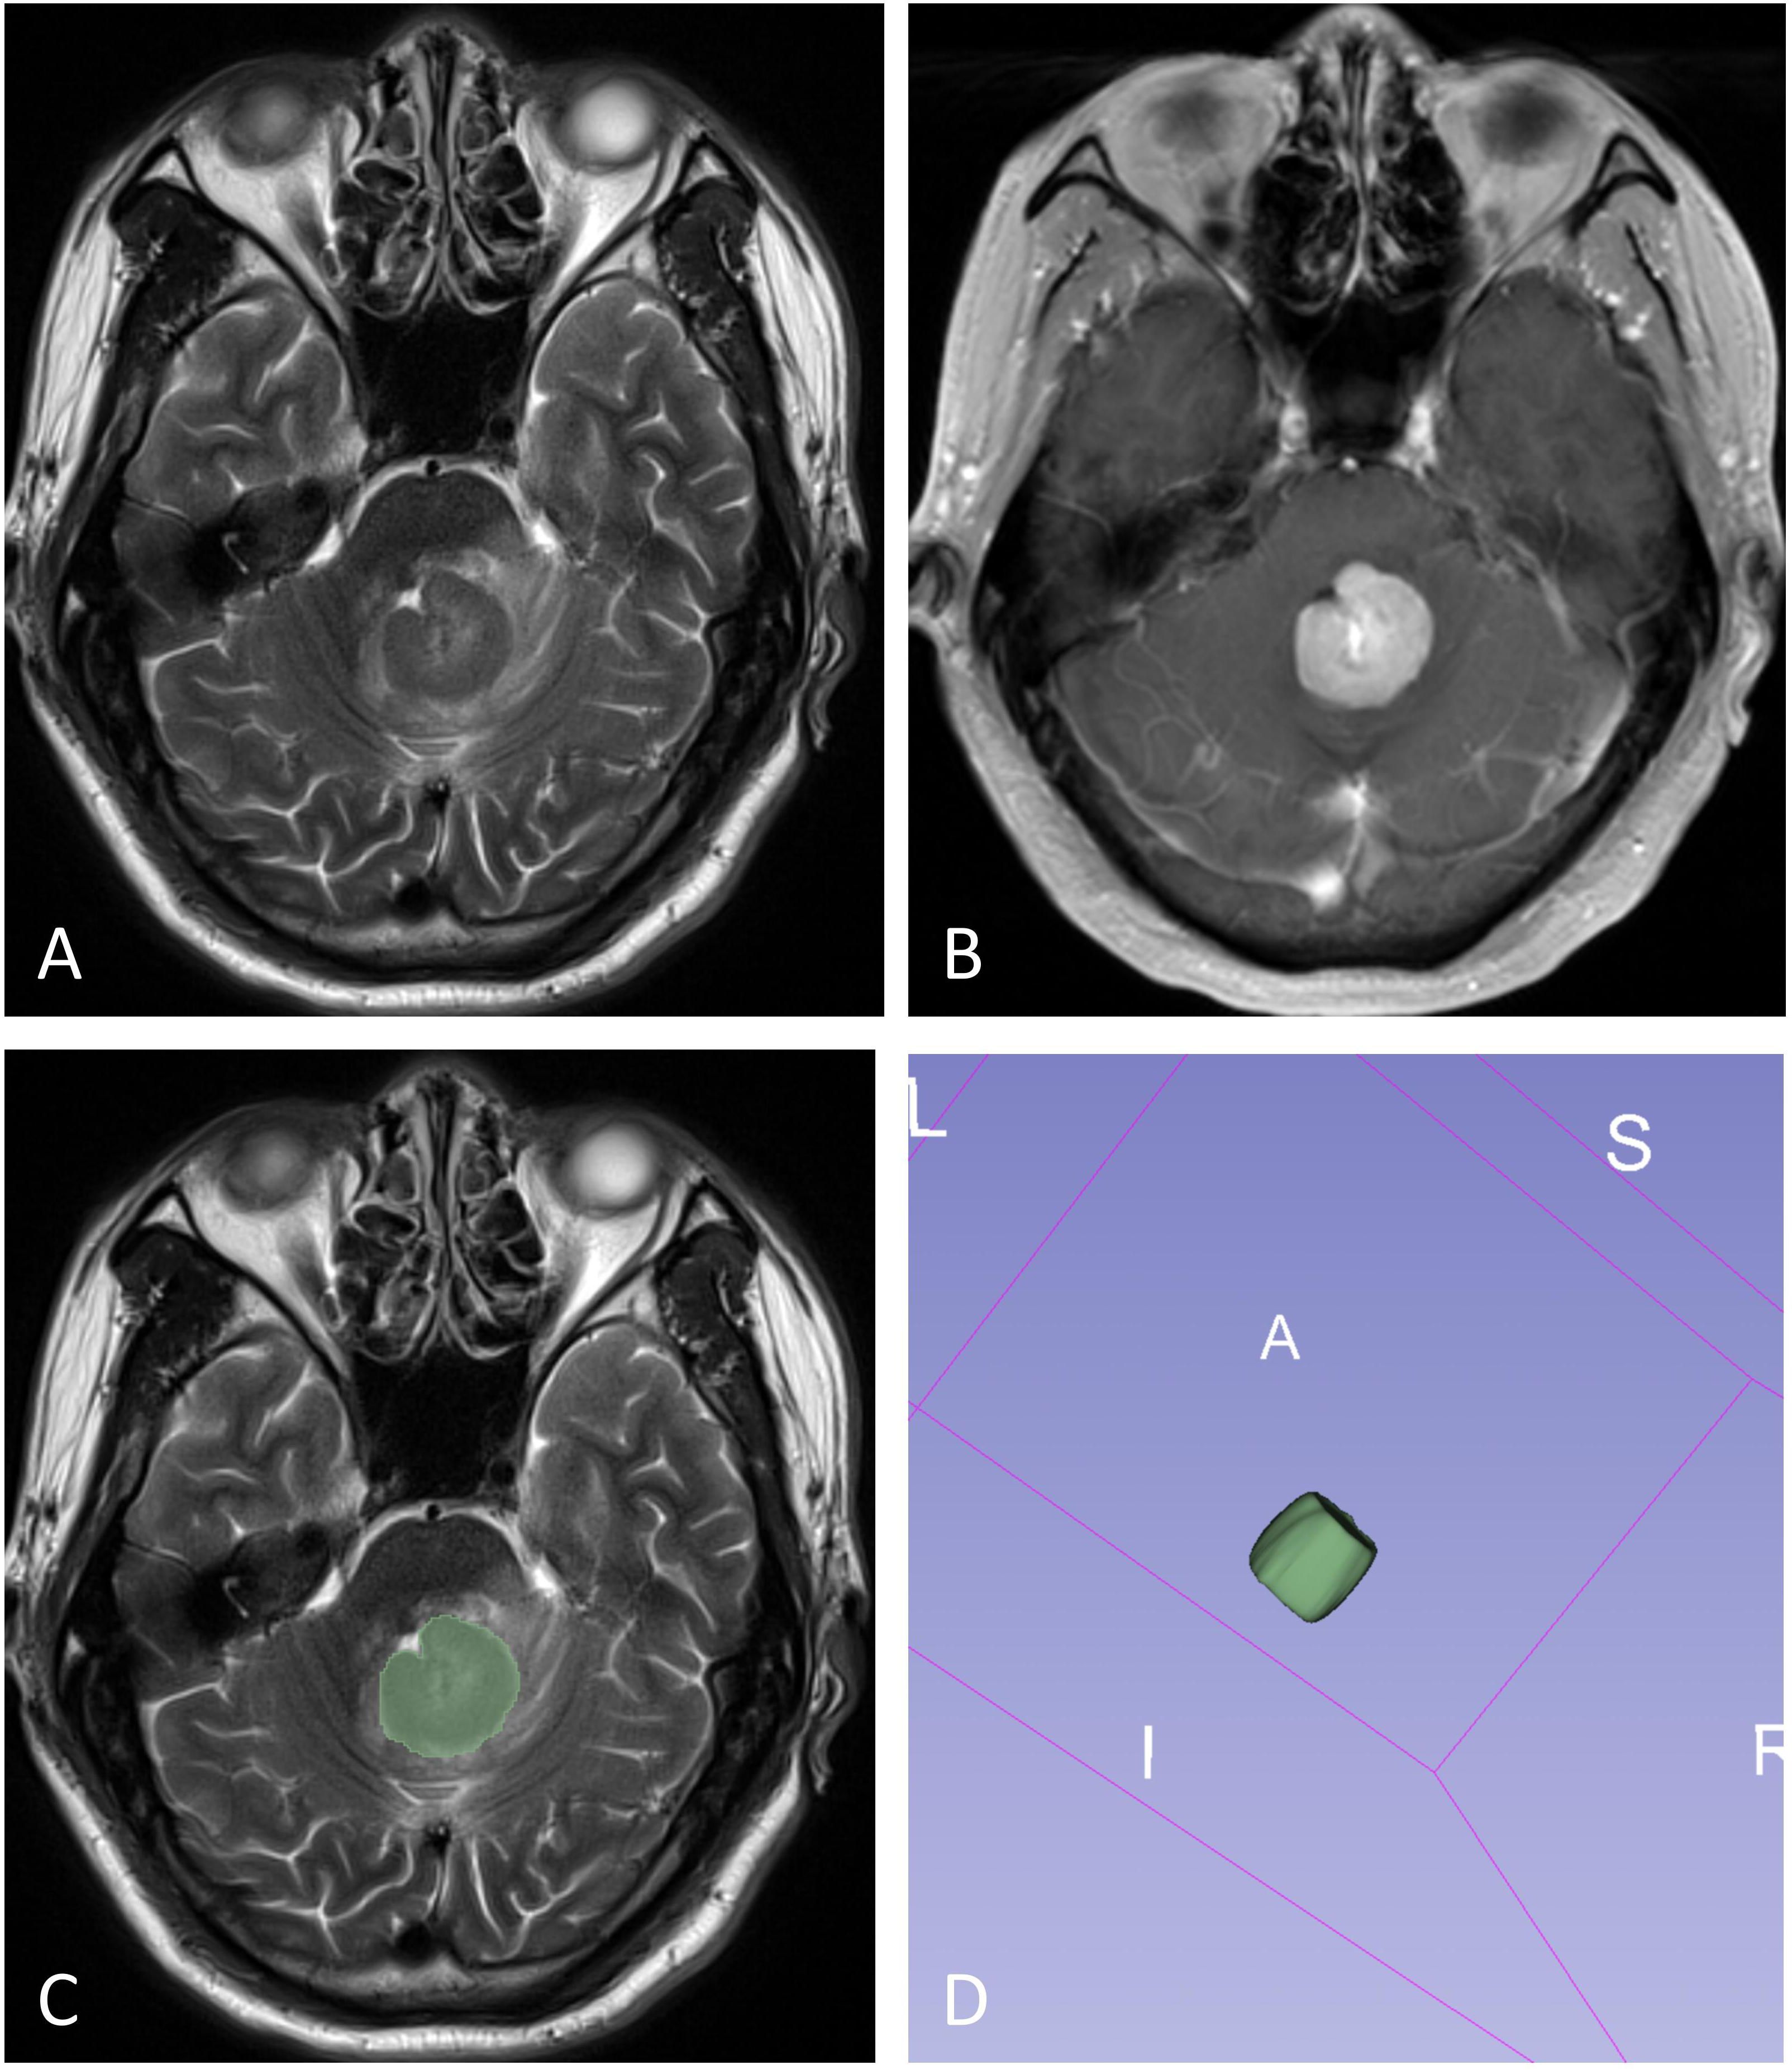

Objective To assess the diagnostic performance of whole-tumor histogram analysis of multiparametric MRI in predicting programmed cell death ligand-1 (PD-L1) expression in primary central nervous system lymphoma (PCNSL). Methods A total of 130 patients with PCNSL (61 males, aged 21-80 years) were included in the study. Histogram features derived from T2-weighted imaging (T2WI), T1-weighted imaging (T1WI), fluid-attenuated inversion recovery (FLAIR), contrast-enhanced T1-weighted imaging (T1WI+C), and apparent diffusion coefficient (ADC) were compared between the low and high PD-L1 expression groups using the Mann-Whitney U test. Receiver operating characteristic (ROC) curves and logistic regression analysis were applied to assess the diagnostic performance of both individual and combined models in predicting PD-L1 expression levels in PCNSL. Results Eighteen histogram features extracted from multiparametric MRI exhibited significant differences between high and low PD-L1 expression in PCNSL (all P < 0.05). The predictive performance of single-sequence models was relatively modest, with areas under the curve (AUC) ranging from 0.637 to 0.705, and no significant differences were observed between these models (all P > 0.05). The combined model demonstrated the highest diagnostic performance (AUC = 0.809), significantly outperforming the single-sequence models (all P < 0.05). Conclusions Whole-tumor histogram analysis of multiparametric MRI shows potential as a non-invasive method for evaluating PD-L1 expression in PCNSL, which may assist in the identification of immunotherapy-eligible patients.